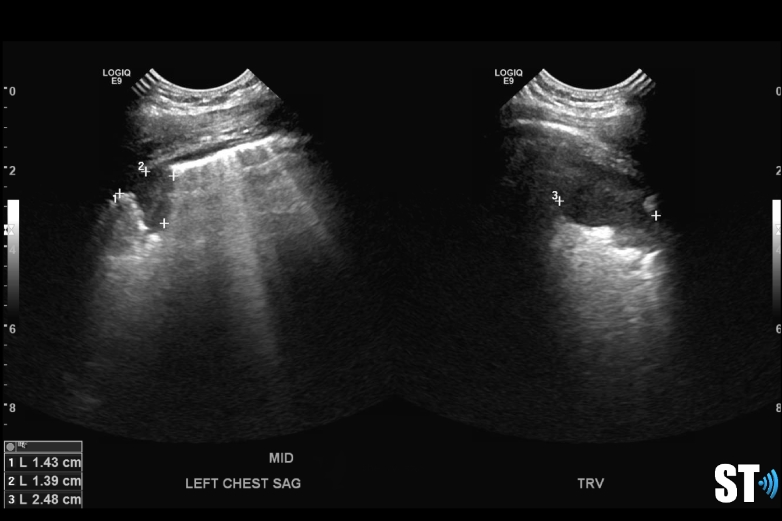

Loculated pleural effusion

complex left pleural effusion

The fluid can be anechoic or echogenic in cases of increased exudates, empyema, hemothorax and chylothorax (lymph collection). There may also be septations.

Large and or symptomatic pleural effusions may be treated with ultrasound guided thoracentesis which can double as a diagnostic procedure, where the fluid removed can be sent to pathology. Normal analysis of the fluid consists of cytology, chemistry and culture.